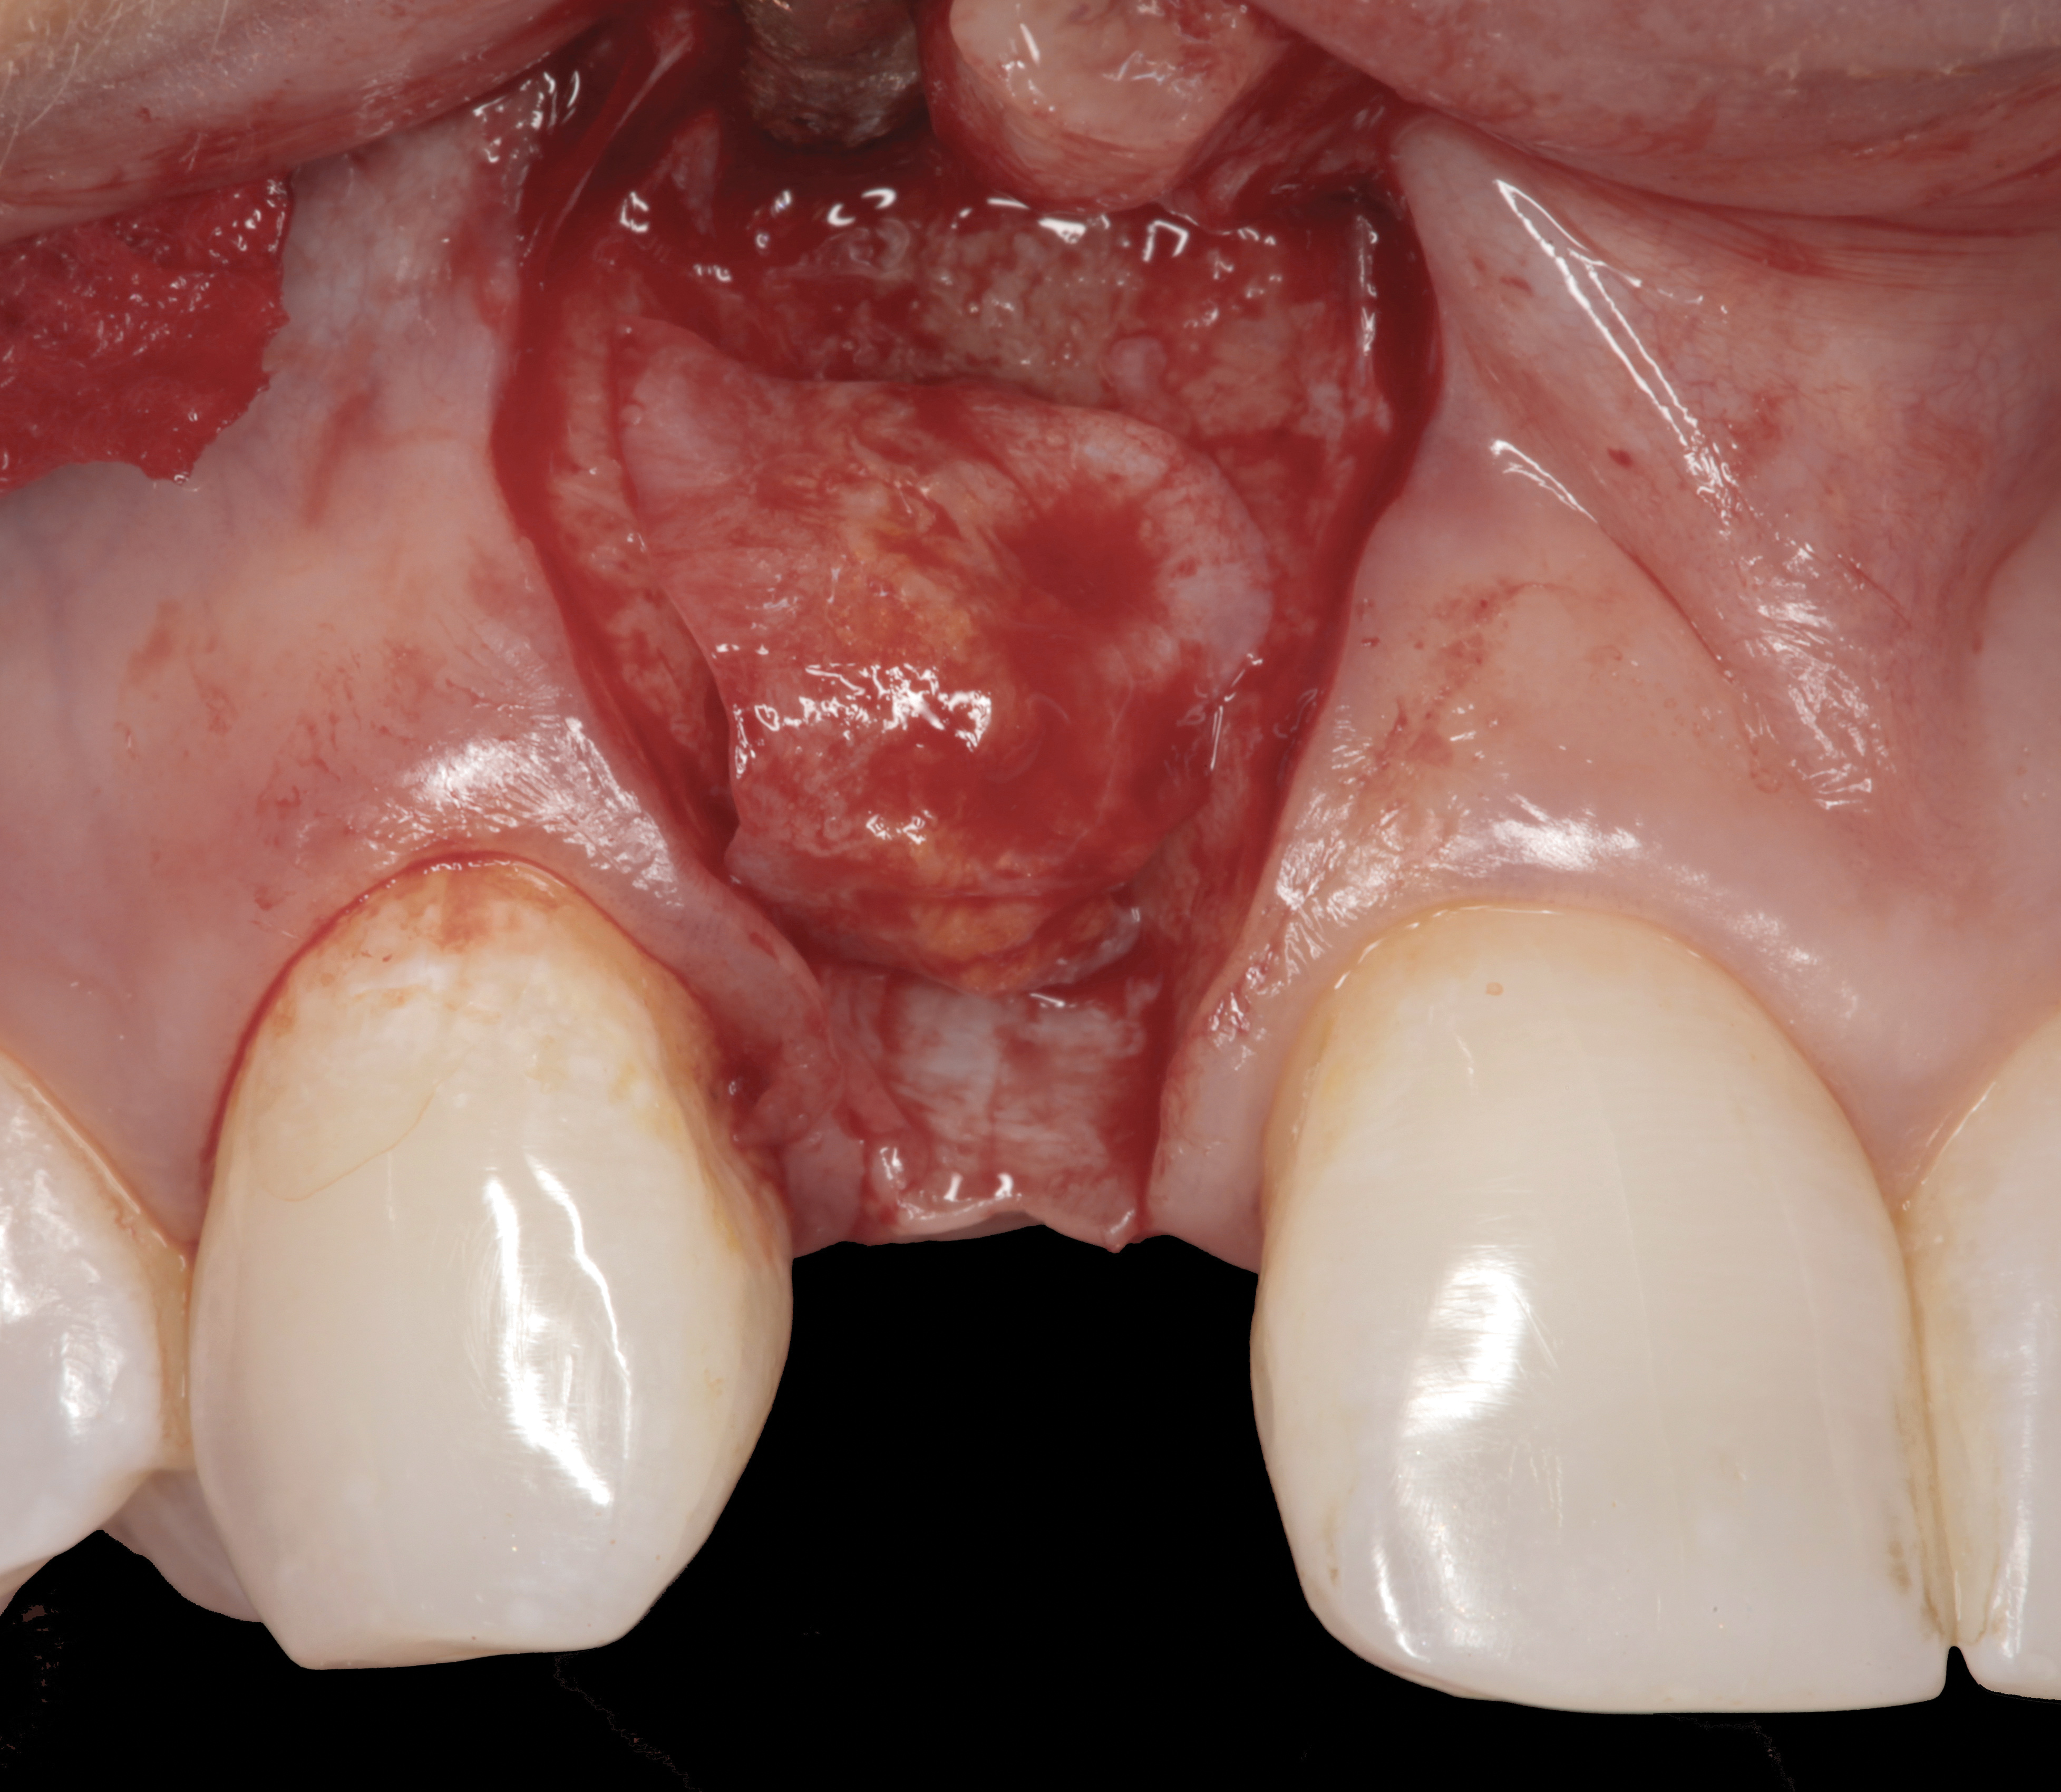

A surgical flap procedure was performed with the intent of thoroughly debriding the granulomatous tissue from the osseous defect (Figure 18 and Figure 19), mechanically and chemically detoxifying the surface of the implant (Figure 20 through Figure 22), and grafting the infrabony component of lesion with bone xenograft (Bio-Oss®, Geistlich Pharma, www.geistlich-na.com) in an attempt to reduce the vertical defect (Figure 23). To concurrently resolve the mucogingival problem, the plan called for placing a dermal allograft (Dermis Allograft, DENTSPLY International, www.dentsply.com) on the buccal (Figure 24) and then replacing the flap (Figure 25).

Fig 18. A full-thickness flap from teeth Nos. 18 to 20 revealed granulomatous tissue in the circumferential defect around implant No. 19.

Fig 19. The circumferential defect was debrided. Note excess cement extending apically from the margin of the crown into the defect; residual cement has been shown to be complicit in the development of peri-implant disease.